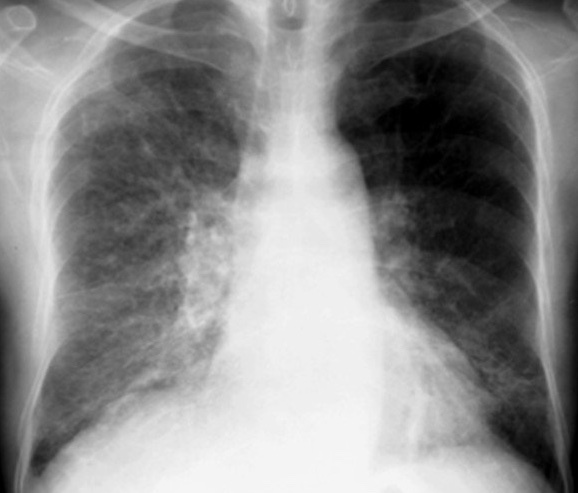

Признаки диффузного фиброза лёгких на рентгенограмме

Что же касается фиброзных изменений в легких, то они свидетельствуют о замещении легочной воздушной ткани с формированием соединительной ткани. Это происходит после перенесенных воспалительных или дистрофических заболеваний легких.

Если фиброзная ткань занимает один или пару сегментов легких, то это не влияет на их функцию. При выраженном распространенном или диффузном пневмофиброзе может страдать газообмен и уменьшаться жизненная емкость лёгких, что проявляется у таких больных одышкой и плохой переносимостью физической нагрузки.